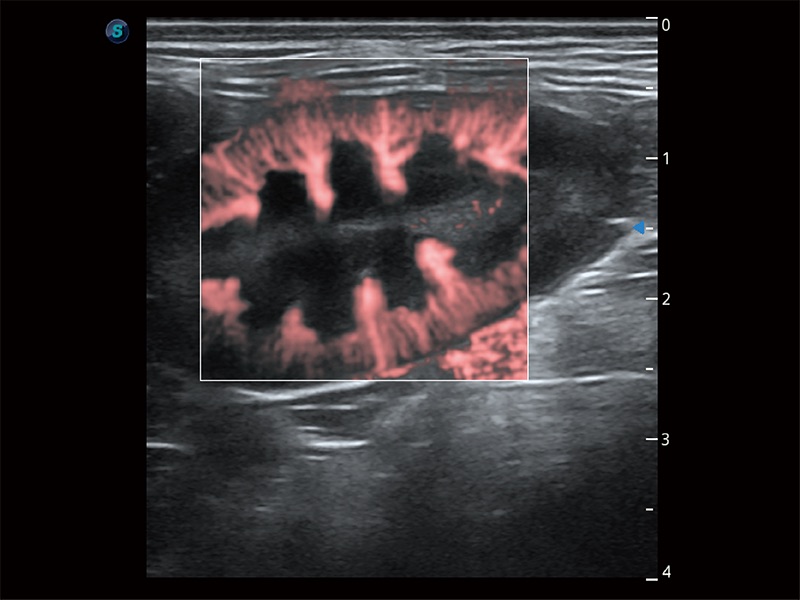

極大提升超低速微細(xì)血流的檢出能力,同時(shí)更精準(zhǔn)地濾除軟組織和超聲信號(hào),為獸用醫(yī)生提供以往無(wú)法通過(guò)常規(guī)血流獲得的疾病診斷信息。

在傳統(tǒng)二維血流成像的基礎(chǔ)上,呈現(xiàn)血流的立體感,具有動(dòng)感的生命力之美。即便是微小的血管也能輕松應(yīng)對(duì),提高了血流的視覺敏感性。